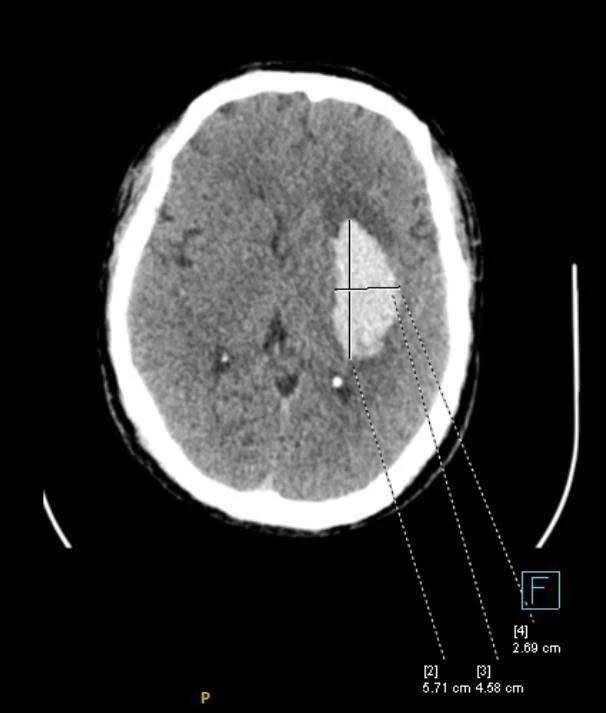

| Ổ tổn thương não do đột quỵ. |

Khi huyết áp tăng vọt, mạch máu não có thể vỡ, gây liệt nửa người hoặc tử vong. Áp lực cao kéo dài cũng làm tổn thương lớp nội mạc mạch máu, khiến mảng xơ vữa bong ra, gây tắc nghẽn động mạch vành, hậu quả là cơn nhồi máu cơ tim cấp. Trái tim phải làm việc quá sức, phì đại dần và cuối cùng suy yếu: theo Framingham Heart Study, tăng huyết áp chiếm tới 75% nguyên nhân suy tim ở người cao tuổi.